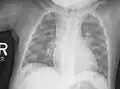

Radiologie

Radiographie conventionnelle aux rayons X d'un enfant de deux ans atteint de rachitisme, présentant un genu varum (fémurs arqués) prononcé, ainsi qu'une diminution de l'opacité osseuse suggérant une faible minéralisation osseuse.

La radiologie confirme le diagnostic, et il est inutile de les multiplier. Le défaut de minéralisation des os longs s'observe particulièrement sur les radiographies de face d'un poignet et des genoux : retard ou irrégularités des points d'ossifications attendus pour l'âge (maturation squelettique), lignes métaphysaires irrégulières donnant un aspect « en toit de pagode », la corticale de la diaphyse est amincie, la densité osseuse est diminuée donnant un aspect vermoulu. Les os longs s'incurvent.

Au niveau du thorax, le chapelet costal clinique donne un aspect radiologique, surtout visible de profil, « en bouchon de champagne » des jonctions chondro-osseuses. En sus des déformations osseuses, on peut observer des atteintes pulmonaires par troubles de la ventilation.